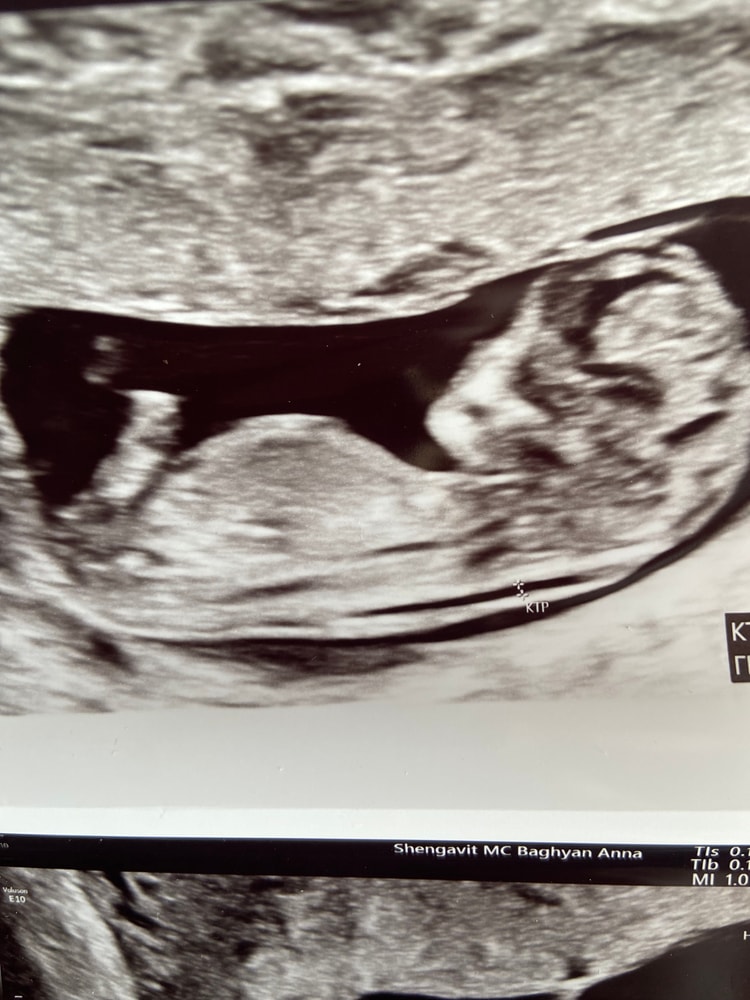

Анализы, скринингиЗдравствуйте, после первой беременности прошло ровно 6 лет и вот наконец получилось долгожданная вторая беременность. Конечно же первым желанием было чтобы малыш был здоровым, но первый у меня богатырь, хотелось принцесску🫣.Настала 12 неделя и на скрининге сказали что по строению малыша-мальчик но полового бугарка еще не было видно. Если есть кто то кто по фото узи может что то сказать буду очень благодарна🥰🥰

Конкретно по вашему снимку я бы не сказала, что видно по строению 100% мальчика, но я и не врач, может у них там какие-то свои критерии наблюдения…

Тут отвернут немного и действительно не очень удачный ракурс,но я бы предположила девочку скорее